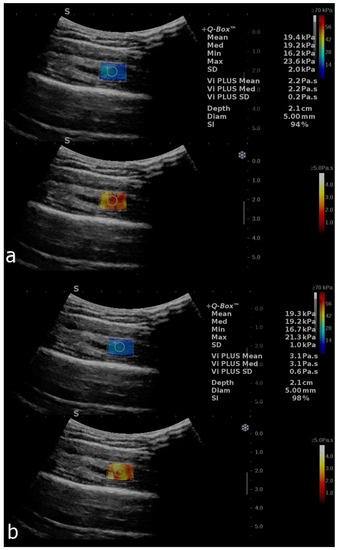

Shear-Wave Elastography and Viscosity PLUS for the Assessment of Peripheric Muscles in Healthy Subjects: A Pre- and Post-Contraction Study

| Variables | Deltoid (Precontraction) Mean ± SD 95% CI of Mean | Deltoid (Postcontraction) Mean ± SD 95% CI of Mean | Soleus (Precontraction) Mean ± SD 95% CI of Mean | Soleus (Postcontraction) Mean ± SD Median (Range) 95% CI of Mean 25–75% Percentile |

| SWE (kPa/s) | 22.2 ± 4.4 [21.2–23.2] | 24.9 ± 5.3 [23.6–26.1] | 13.1 ± 4.7 [12–14.1] | 14.2 (4.2–31.7) [25% 11.3–75% 18.5] |

| ViPLUS (Pa.s) | 2.9 ± 0.5 [2.8–3] | 3.1 ± 0.5 [3–3.2] | 2.1 ± 0.5 [1.9–2.2] | 2.4 ± 0.6 [2.3–2.6] |